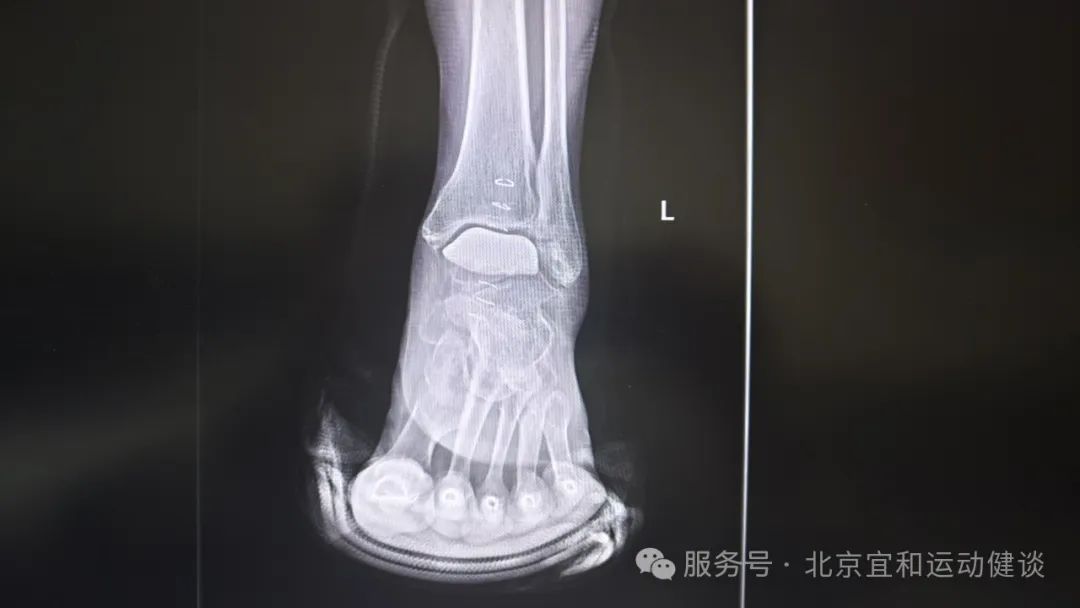

武主任和赵主任看了莉莉阿姨的影像学检查资料后,确诊莉莉阿姨是【踝骨关节病】,且距骨关节面已经明显损伤,最适合的手术方案是踝关节部分置换。

患者术前影像学检查资料